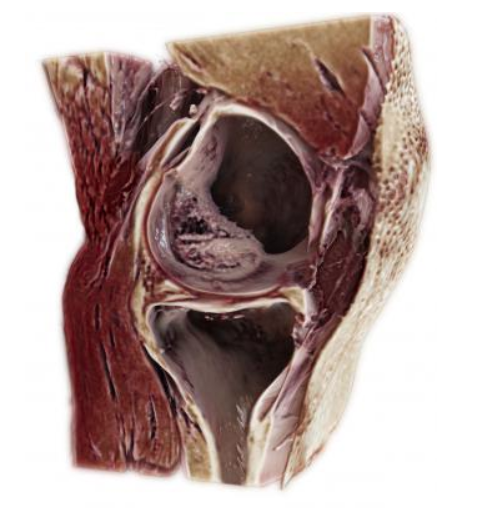

Materialise and Formlabs are collaborating to deliver a complete, cost-effective and easy-to-use solution for hospitals looking to start an in-house 3-D print lab. The new offering combines the Materialise Mimics inPrint medical imaging software with Formlabs’ Form 2 professional-grade desktop 3-D printers. The components of this complete 3-D printing package facilitate the implementation of patient-specific care at an affordable price-per-print for quick return on investment.